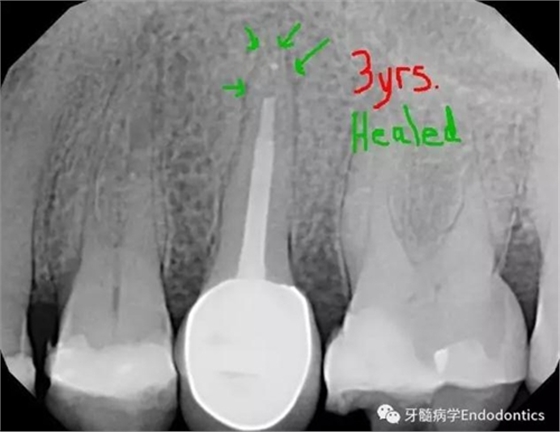

圖5.術(shù)后3年